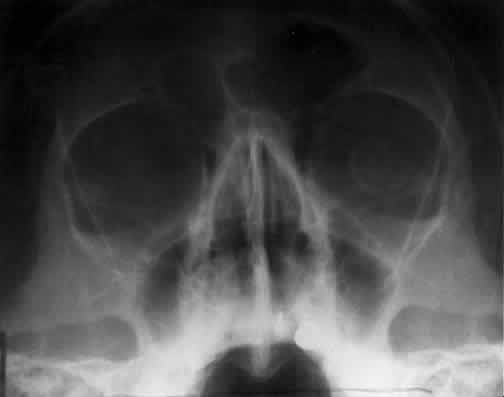

Bony destruction usually results from a rapidly growing process such as a tumor of the lacrimal gland or paranasal sinuses (Fig. 12). Sinusitis or a mucocele can also cause bone destruction or dehiscence of the orbital bones. Mucoceles most often originate in the frontal and ethmoid sinuses, and destruction of bone is noted radiographically in 70% of cases24 (Fig. 13). Encephaloceles may also cause a disruption in the orbital bones, usually superomedially. Neurofibromatosis is associated with dysplasia that can involve large segments of the greater wing of the sphenoid. Pulsating exophthalmos may be a clinical finding.

Fig. 13. Frontal sinus mucocele extending into the right orbit. The orbital extension was responsible for downward displacement of the globe in this patient. The frontal sinus is the most frequent origin for mucoceles.